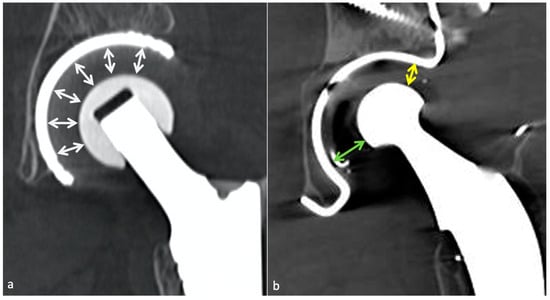

4.5.2. Classification and Contribution of Imaging Methods

- Metallosis results from the shedding of metallic debris (secondary to a MoM prosthesis with corrosion, a conflict between a metallic acetabular cup and the prosthetic neck, or a contact between a metallic head and an acetabular metal back in case of PE wear or dislocation) that induces synovitis and an indolent pattern of osteolysis, potentially leading to loosening (i.e., potentially looking similar to osteolysis and PE wear). Synovitis may contain low-signal intensity or metallic density debris, causing MRI artifacts and bone erosion, best depicted on CT-MAR (Figure 20). Such debris might also be located in periprosthetic soft tissue and lymph nodes [54,57]. Metallic debris presence might also accentuate PE wear (i.e., third fragment wear) [54]. Of note, high serum metal-ion levels can be found in symptomatic and asymptomatic patients and would be associated with pseudo-tumors, so that such a biological finding should lead to the prescription of an MRI to rule out a pseudo-tumor even in asymptomatic patients [6,103].